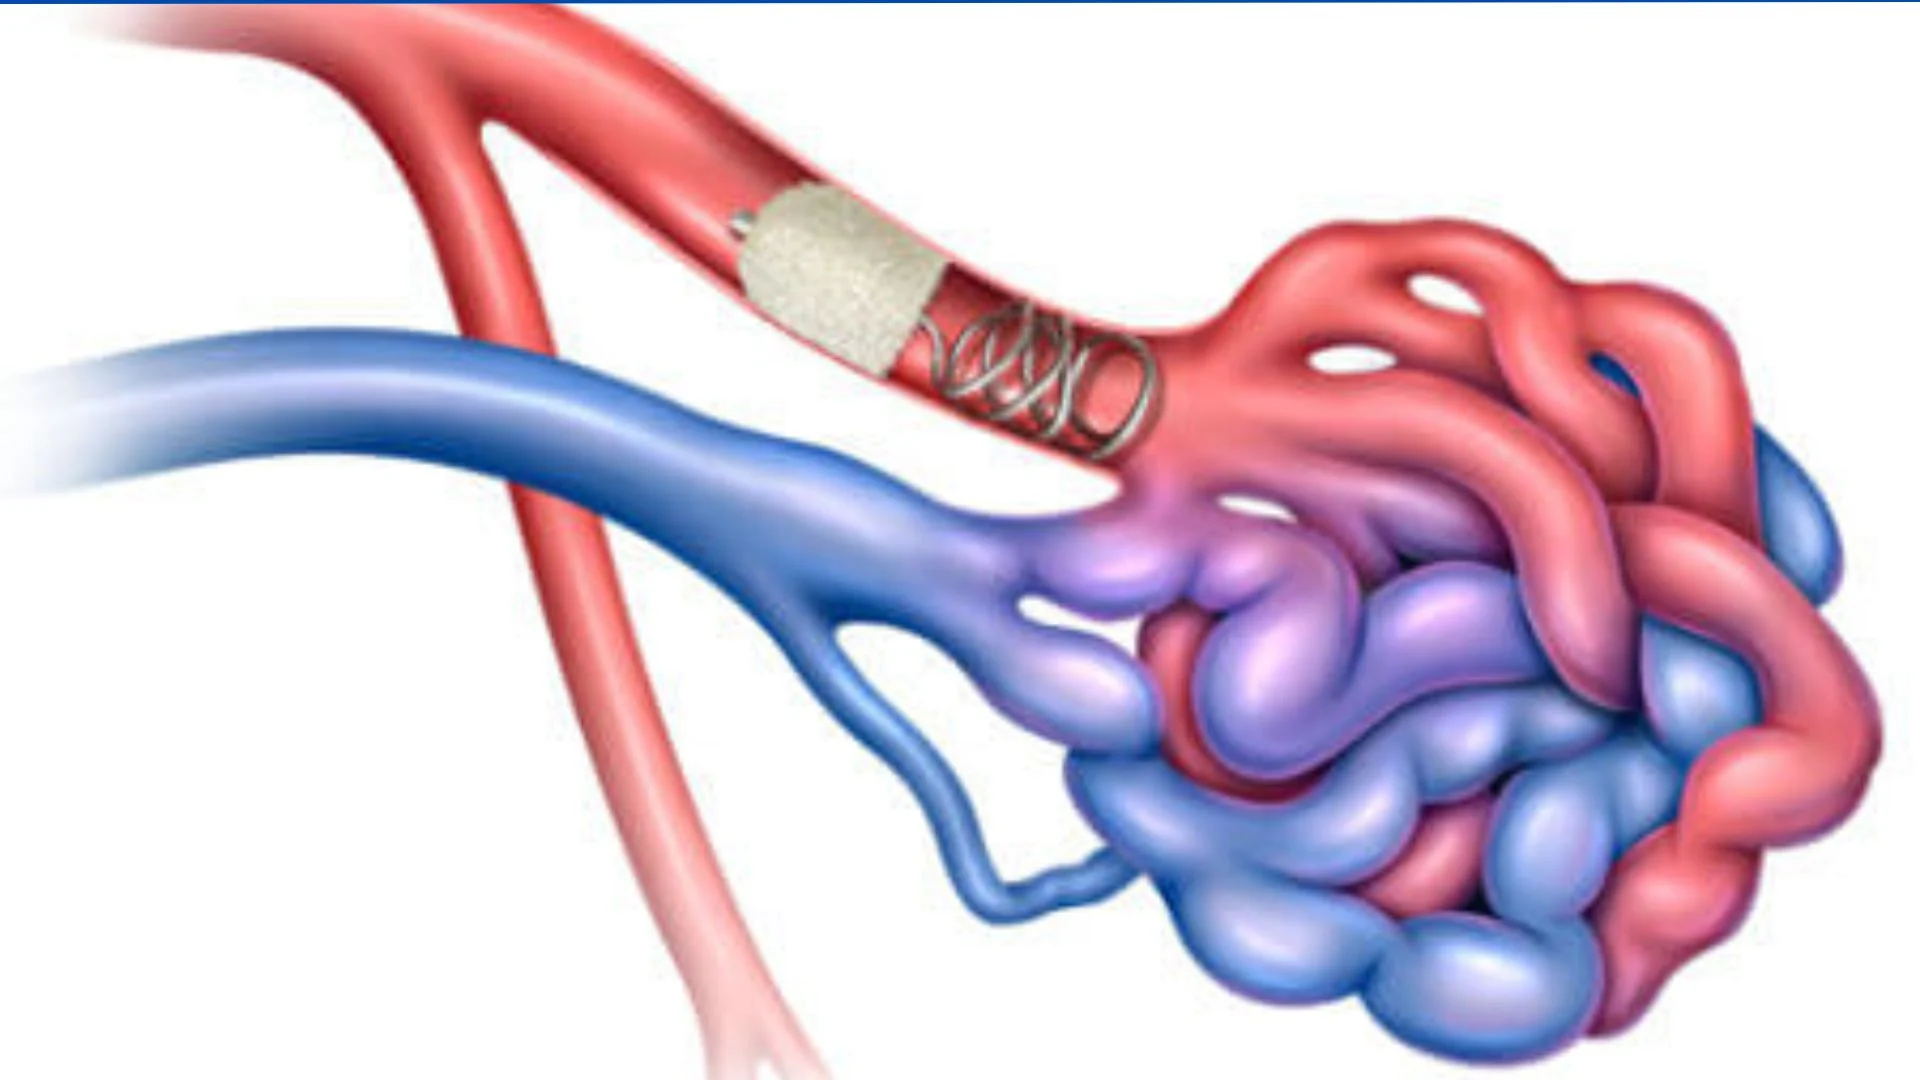

AVM embolization is a minimally invasive procedure that targets and blocks abnormal blood vessels in an arteriovenous malformation (AVM). This treatment is particularly important for AVMs located in the brain, as they can lead to severe neurological damage if they rupture.

AVM embolization is a minimally invasive procedure that targets and blocks abnormal blood vessels in an arteriovenous malformation (AVM). This treatment is particularly important for AVMs located in the brain, as they can lead to severe neurological damage if they rupture.

- AVM embolization may be used as a standalone treatment or in combination with other surgeries.

- It helps reduce the risk of bleeding and can decrease the size of the AVM.

- It can also alleviate stroke-like symptoms, improving overall patient outcomes.